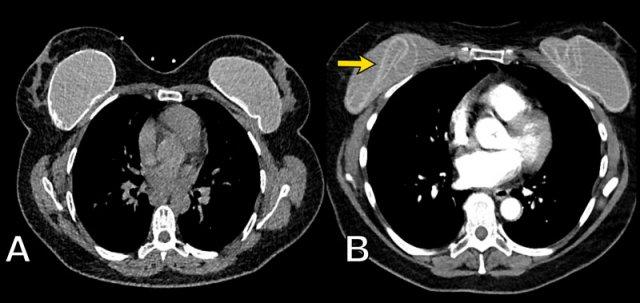

X-Quang và CT

X-Quang ngực và CT không đóng vai trò trong việc khảo sát túi ngực nhân tạo.

Đôi khi chúng có thể được phát hiện trên X-Quang, chẳng hạn khi có vôi hóa bao xơ hoặc khi nhìn thấy van bơm của túi giãn nở (mũi tên).

Phim ngực thẳng cho thấy vôi hóa bao xơ trong một túi ngực nhân tạo bị di lệch vào trong, không song song với đường viền tuyến vú.

CT của cùng bệnh nhân này cũng cho thấy vôi hóa ở mặt sau không đi theo đường viền của túi ngực, gợi ý vỡ túi trong bao xơ (mũi tên).

Một túi ngực còn nguyên vẹn có tỷ trọng bên trong đồng nhất màu xám trên CT, với lớp vỏ bao và bao xơ mỏng bao quanh có tỷ trọng cao hơn một chút.

Trên CT có thể thấy các loại van bơm khác nhau của túi ngực nhân tạo.

Vôi hóa bao xơ thường gặp và đôi khi có thể thấy dấu hiệu Linguine (mũi tên).

Trong hầu hết các trường hợp, các phát hiện trên CT sẽ không có tính kết luận.

Túi ngực bên trái của bệnh nhân này cho thấy vôi hóa bao xơ không nằm ở ngoại vi và có tính chất gián đoạn.

Chưa rõ đây là vỡ túi ngoài bao xơ hay có tràn dịch lượng nhiều.